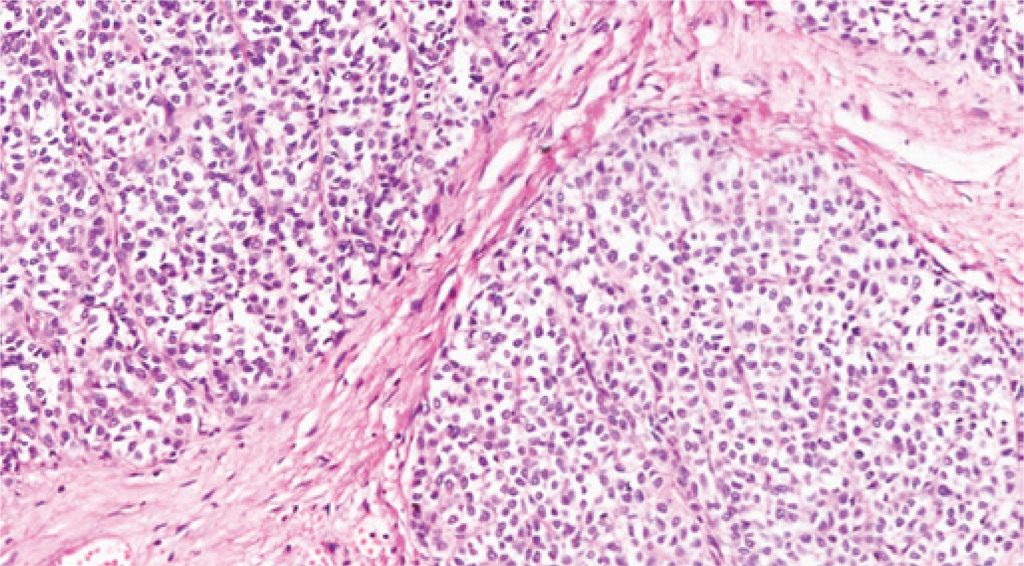

Figure 4

Histology – epithelioid neoplasm, with medium-sized cells, irregular nuclei, in organoid arrangements and blocks - 8 mitosis per 10 HPF, with necrotic foci